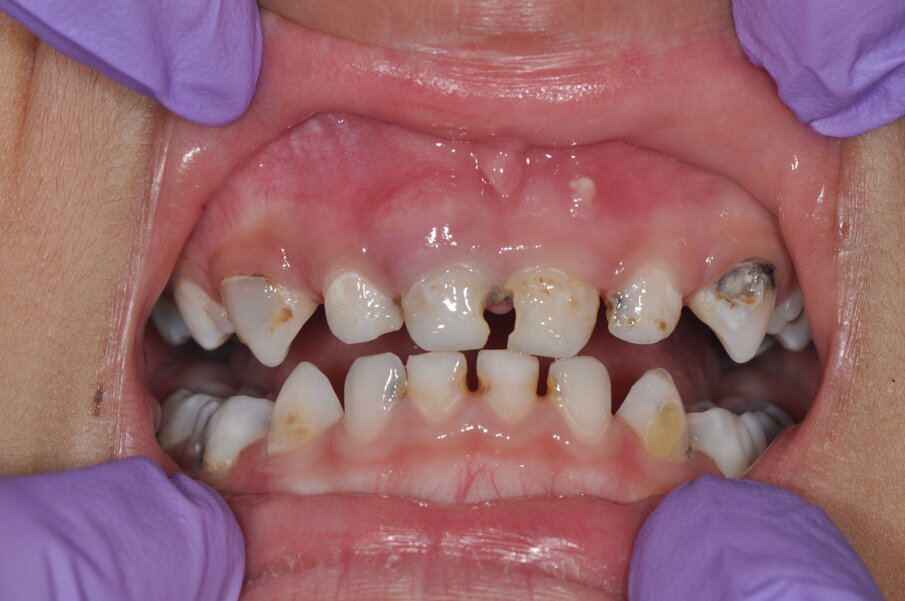

A 4-year-old girl was referred to the Children’s Dental Center in Gurgaon in India with the complaint of painful teeth when eating and the presence of unsightly maxillary anterior teeth. Clinical examination showed large carious lesions in the maxillary anterior teeth (Fig. 1). A radiographic examination showed pulpal involvement of caries in teeth #51 and 61 (Fig. 2).

Fig.1: Caries associated with the four front teeth.

Fig. 11: Preoperative situation.